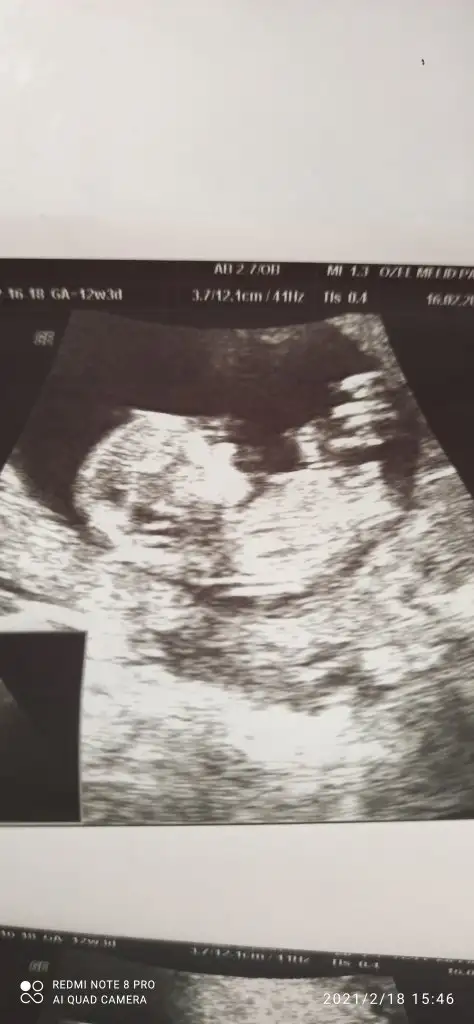

Erkek gibi 12-13 hafta olursa paylaşın emin olamadım11+6 olduk biz cinsiyet tahmininiz var mı

Acısı 30° canım belkide ileri haftada yükselir başka USG varsa paylaşın 11+4 USG erkekte olabilirTamam canım teşekkür ederim doktor /80 erkek dedi ama değişebilir dedibir kızım var hayırlısı ne ise o olsun

Acısı 30° canım belkide ileri haftada yükselir başka USG varsa paylaşın 11+4 USG erkekte olabilir13 haftada nubu tam net olur aslında oranları ilk sayfaya yazmıştım

13 değil 11+4 ayAcısı 30° canım belkide ileri haftada yükselir başka USG varsa paylaşın 11+4 USG erkekte olabilir13 haftada nubu tam net olur aslında oranları ilk sayfaya yazmıştım